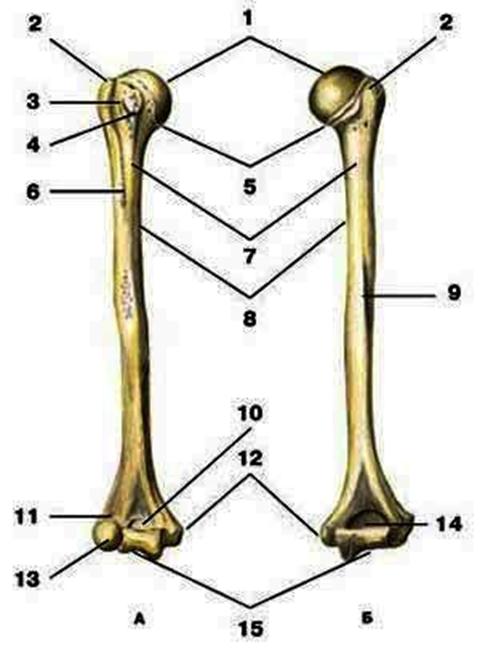

V2:Тема 1.3 Кости верхней конечности и их соединения

S: Цифра 1 обозначает … плечевой кости.

+:сaput

-:t uberculum majus

-:troсhlea

-:capitulum

-:epicondylus lateralis

S: Число 15 обозначает... плечевой кости.

+:trochlea

S: Цифра 5 указывает на...плечевой кости.

+:collum anatomicum

S: Число 10 обозначает... плечевой кости.

+:fossa coronoidea

S: Число 14 указывает на... плечевой кости.

+:fossa olecrani

S: Цифра 9 указывает на... плечевой кости.

+:sulcus nervi radialis

S: Число 12 обозначает... плечевой кости.

+:epicondylus medialis